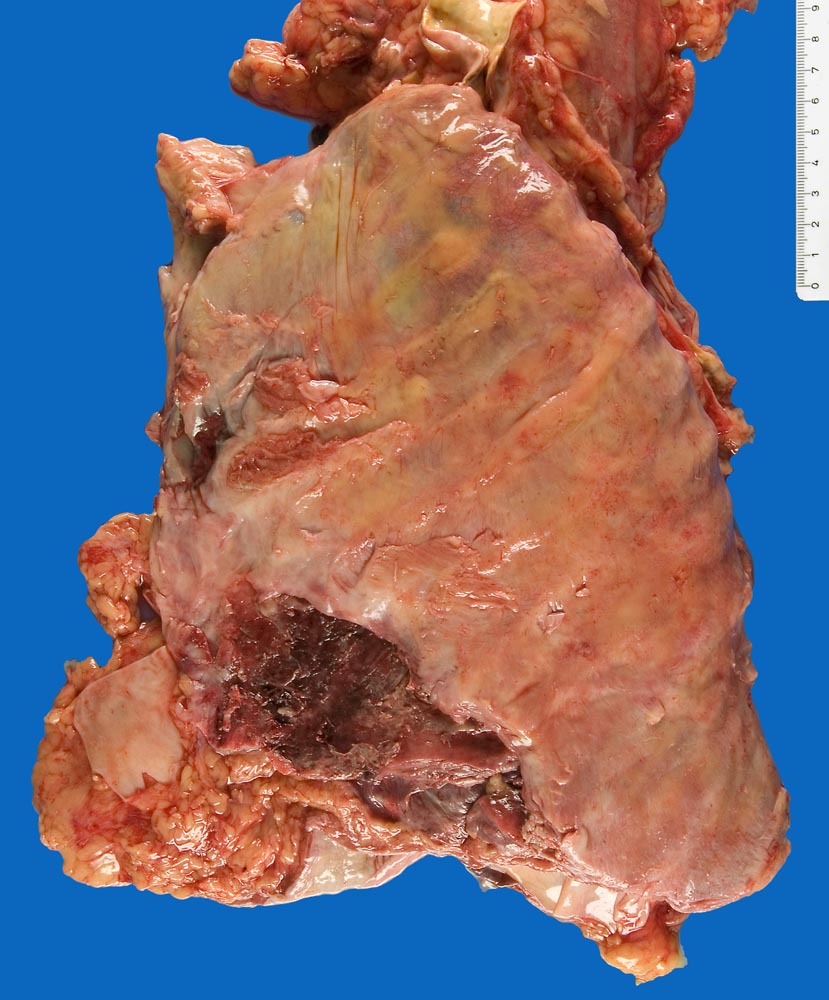

Pleuraschwarte nach Talkpleurodese

Massive schwartige Verdickung der Pleura.

Asbestnachweis in der Lungenveraschung (Asbestexposition laut klinischen Angaben).

Talkpleurodese der linken Lunge (vor 6 Wochen) bei rezidivierenden Pleuraergüssen seit 8 Monaten